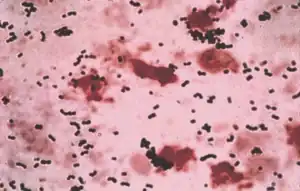

| Streptococcus agalactiae- Gram stain | |

As mentioned, S. agalactiae is a Gram-positive coccus with a tendency to form chains, beta-haemolytic, catalase-negative, and facultative anaerobe. GBS grows readily on blood agar plates as microbial colonies surrounded by a narrow zone of β-haemolysis. GBS is characterized by the presence in the cell wall of the group B antigen of the Lancefield classification (Lancefield grouping) that can be detected directly in intact bacteria using latex agglutination tests.[18][19][20]